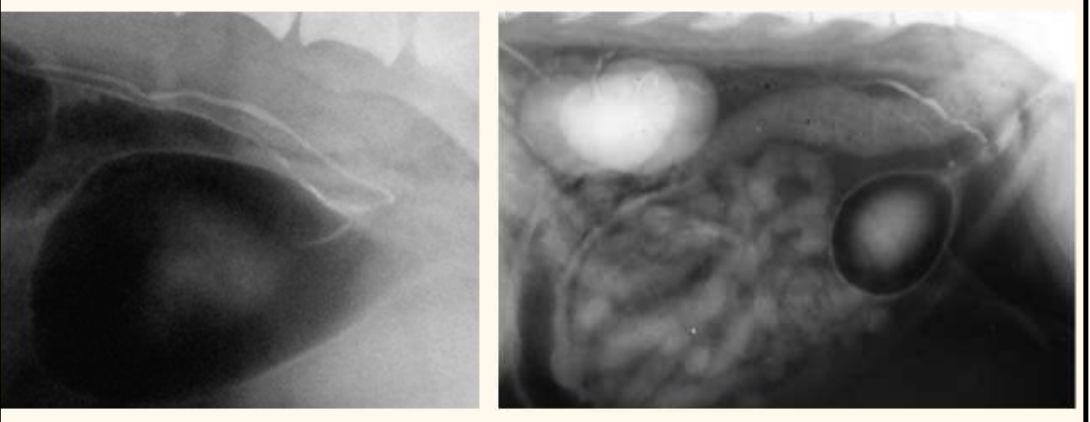

Contrast radiography – IV urogram with pneumocystogram

contrast radiography. what does this px have

air -ve contrast

whats wrong with this patient

ectopic ureter— hydroureter